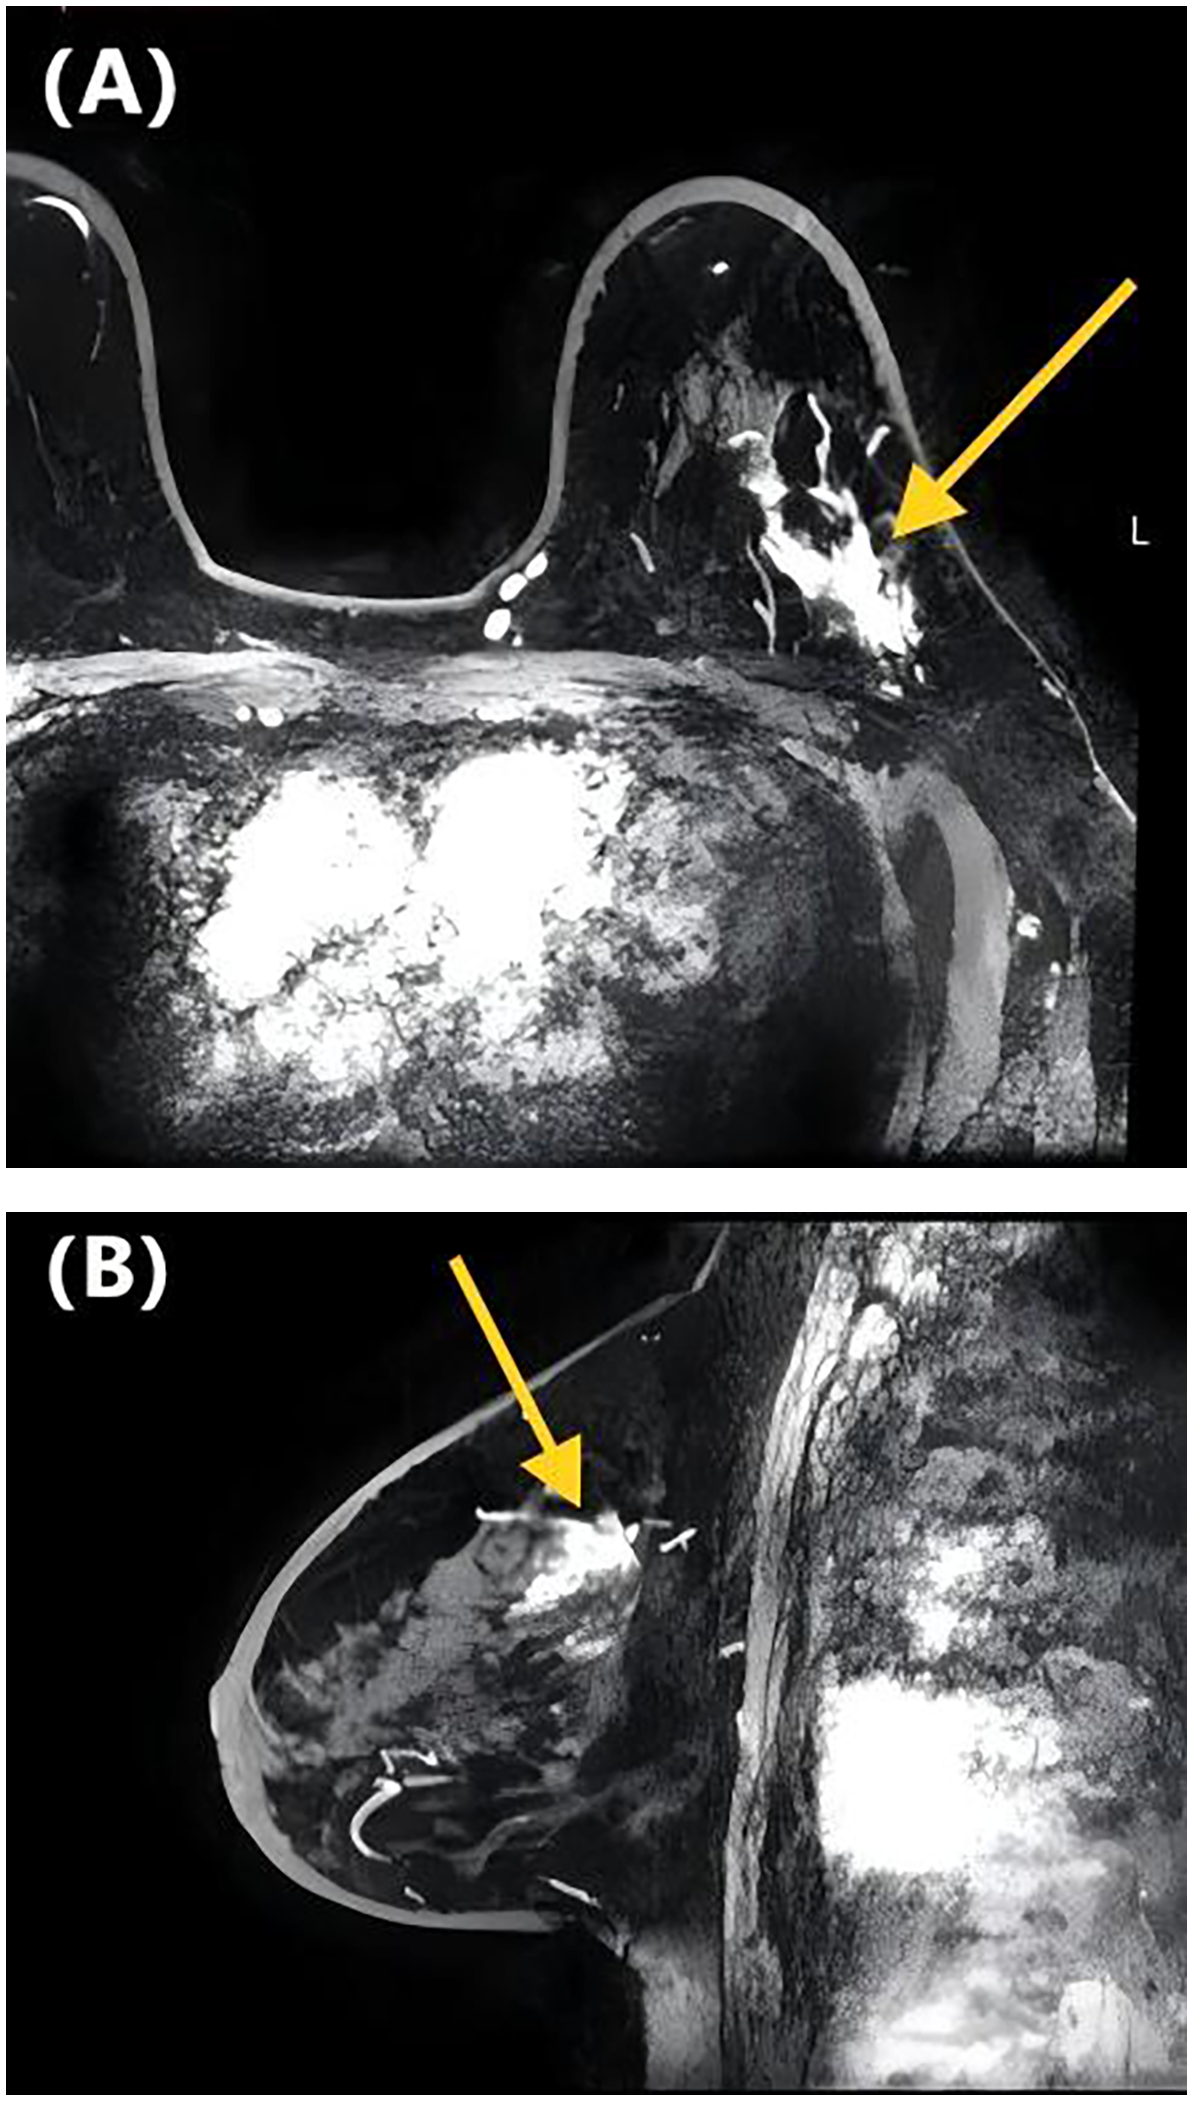

Table 2 presents the GVIF analysis used to assess multicollinearity. The regression model demonstrated an absence of significant multicollinearity, as all adjusted GVIF values were below 2.24 except for PR status. Although the GVIF for PR status exceeded 2.24, it remained below the 3.16 tolerance threshold, indicating acceptable collinearity levels. After controlling for confounding factors through multivariate logistic regression analysis, four risk factors associated with LVI formation were identified (Table 3). Patients aged ≥45 years (OR = 0.406, 95% CI: 0.191-0.844, P = 0.017) and those with higher ADC values (OR = 0.133, 95% CI: 0.017-0.825, P = 0.041) had a lower risk of LVI formation. Among the NME distribution patterns, patients with linear distribution had a significantly higher risk of LVI positivity compared to those with focal distribution (OR = 13.540, 95% CI: 1.390-172.644, P = 0.030) (Figures 1, 2), while no statistically significant differences were found for segmental, regional, multiple region, or diffuse enhancement patterns (all P > 0.05). Regarding molecular subtypes, compared to the Luminal A subtype, patients with Luminal B (OR = 5.081, 95% CI: 1.326-33.859, P = 0.039), HER2 overexpression (OR = 9.378, 95% CI: 1.922-71.460, P = 0.012), and triple-negative subtype (OR = 11.599, 95% CI: 2.043-96.710, P = 0.010) had a significantly higher risk of LVI formation.

Figure 2

DCE-MRI images of a 65-year-old woman with invasive ductal carcinoma of the left breast. Axial contrast-enhanced image (A) and sagittal contrast-enhanced image (B) show non-mass-like enhancement with the focal distribution. Lymphovascular invasion was negative at the histopathological examination.